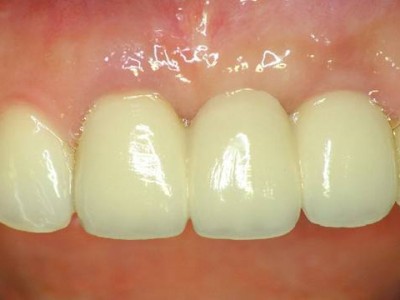

환자의 치아 모양·색상에 맞춰 맞춤 제작된 크라운을 부착해 자연스러운 심미성과 기능을 회복합니다.

A+ 임플란트의 다양한 케이스를 확인해보세요.